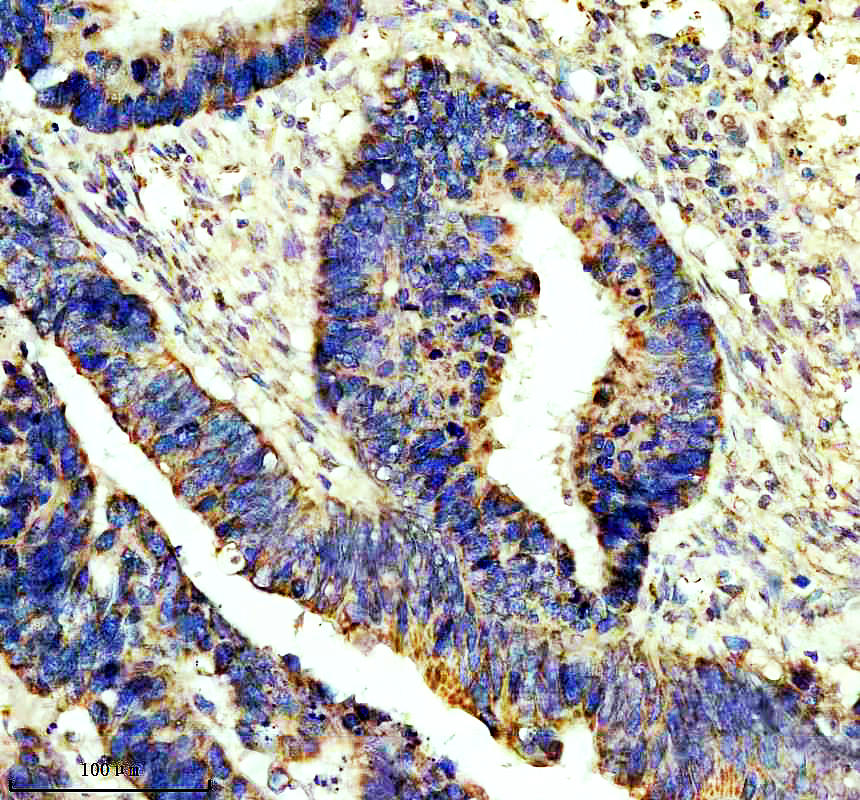

• IHC analysis of 14-3-3 GAMMA/YWHAG-Specific using anti-14-3-3 GAMMA/YWHAG-Specific antibody (A04148-2).14-3-3 GAMMA/YWHAG-Specific was detected in a paraffin-embedded section of human esophageal squamous carcinoma tissue. Biotinylated goat anti-rabbit IgG was used as secondary antibody. The tissue section was incubated with rabbit anti-14-3-3 GAMMA/YWHAG-Specific Antibody (A04148-2) at a dilution of 1:200 and developed using Strepavidin-Biotin-Complex (SABC) (Catalog # SA1022) with DAB (Catalog # AR1027) as the chromogen.